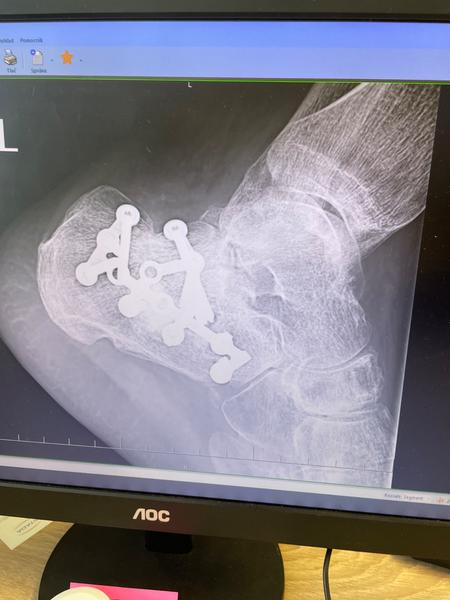

Trieštivá zlomenina päty

Ahojte,, chcem reagovať Mariane na mail a hlavne držim palce Tvojmu manželovi. Čaka ho beh na dlhú trať. Ja som tiež myslel, že to do dvoch mesiacov dám. Som zhruba rok po operácií a poviem, že kto to raz zažije tak nikdy viac. Radšej zlomená kosť, ale nie trieštivá zlomenina.päty. V prvom rade musí čim skôr začať cvičiť. Ak pôjde do kúpeľov veľký pozor na vodu, nech si to rozdelí s väčším odstupom, nie po sebe. Dobre bude plávanie a cyklistika, ale s mierou. V žiadnom prípade nech nedáva saunu. V nohe má Titan a ak mu ho nebudú vyberať, nevieš čo môžu spôsobiť zahriatie. Predsa sú tam skrutky, ktoré pri povolení môže spôsobiť zápaľ. Držim palce.